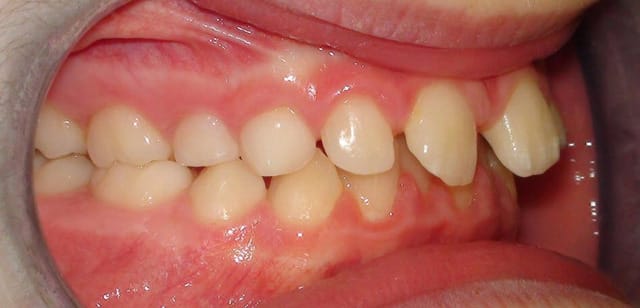

Je vous joins également pour faire plaisir à certains des photos intra-buccales bien qu'elles n'apportent absolument rien de plus.

si, si, si, classe d'angle, ddm, supraclusion, volume des arcades, etc...

OK, on voit une supraclusie incisives, mais pas de DDM et j'en aurais parlé dès le départ si ça avait pu apporter quelque chose au plan de traitement.

Et on voit aussi la vestibuloversion de la 22 qui est effectivement un signe positif d'inclusion vestibulaire de la canine. Dans ce sens, tu as raison.